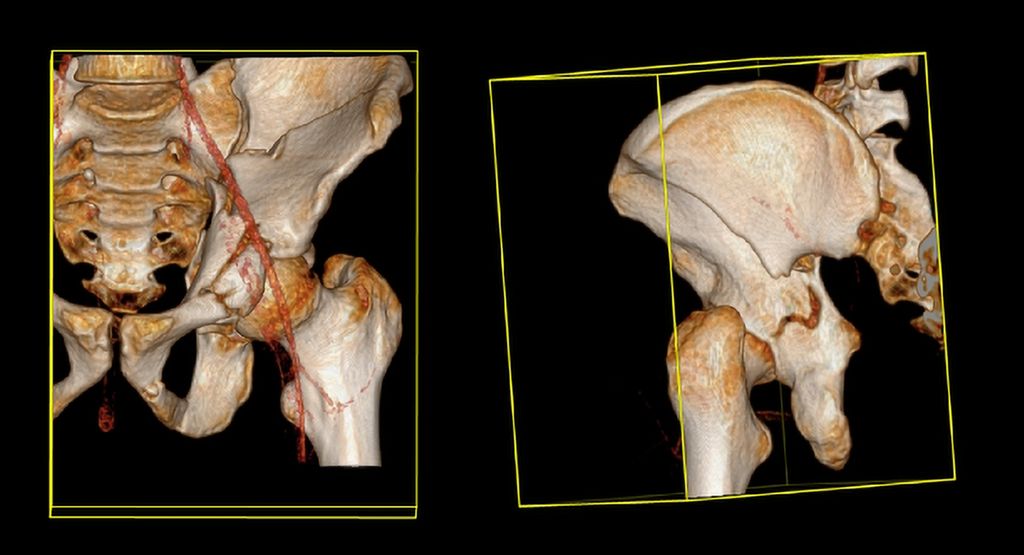

Die Mehrheit der Herausforderungen bei der Behandlung der Fragilitätsfraktur des Acetabulums überschneidet sich mit denen bei Beckenringfraktur. Ebenso wenig überraschend treten auch auf der anderen Seite des Hüftgelenkes ähnliche Komplikationen und eine Reduktion der Lebenserwartung wie bei hüftnahen Oberschenkelfrakturen auf. Im Unterschied zu den FFP gilt dieselbe Klassifikation für Hochrasanz- und Niedrigenergietraumata des Acetabulums nach Judet und Letournel. Der große Unterschied besteht jedoch in der Häufigkeitsverteilung. Aufgrund der meist einfachen Stürze mit Gewalteinwirkung über den Trochanter major betreffen die Fragilitätsfrakturen des Acetabulums meist den vorderen Pfeiler und die quadrilaterale Fläche. Entsprechend sind dislozierte Frakturen eine Domäne der offenen Operationsverfahren und der Hüftendoprothetik. Der Stellenwert der minimalinvasiven Stabilisierung nicht dislozierter Acetabulumfrakturen und der Stabilisierungen in Fehlstellung ist wissenschaftlich nicht geklärt. Jedoch gibt es zunehmende Literatur über das sogenannte „fix and replace“, bei dem eine Osteosynthese eines Pfeilers mit einer primären Totalendoprothese in einer Operation kombiniert wird (Abb. 2).

Die „Fix and replace“-Behandlungsoption ist gerade für Zwei-Pfeiler-Frakturen interessant, da bei dieser häufigen geriatrischen Frakturform aufgrund der vorliegenden sakroiliakalgelenksnahen Beckendiskontinuität selbst durch gängige Revisionspfannen nicht immer eine Belastungsstabilität erreicht werden kann (Abb. 3).